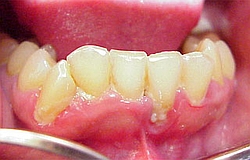

Mit etwas Einsicht wird alles noch gut. Zähne und Zahnfleisch wurden sich selbst überlassen für lange Zeit

Erst der Schmerz trieb den Patient in die Zahnarzt Praxis.

Manchmal traut sich auch der Patient die schmerzhafte Zone nicht mehr zu putzen, was alles aber schlimmer macht

Parodontitis = akute Zahnfleischentzündung kann auch bei guter Pflege entstehen, sehr schmerzhaft und beeindruckend aber schnell heilbar ohne Verlust

Parodontose = chronische Zahnfleischentzündung mit Knochenverlust und Verlust des Zahnhaltes bei fortgeschrittenem Zustand. Muss über einen längeren Zeitraum immer wieder kontrolliert werden.